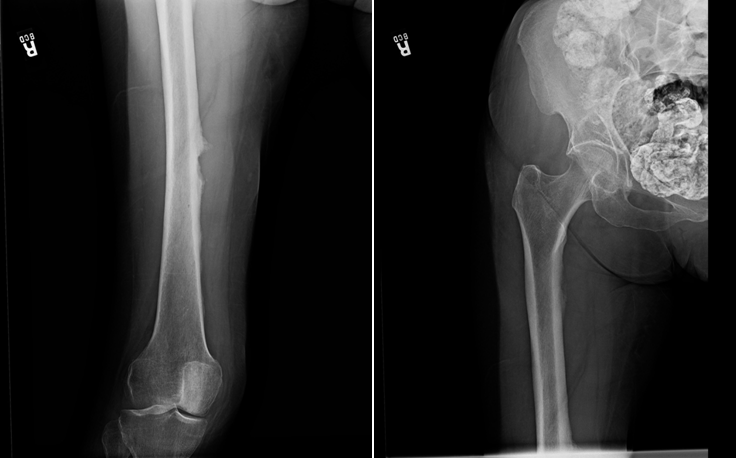

A 79-year old female presents with complaints of right hip pain for 2 months. She denies prior injury or precipitating event. The pain is made worse by lying on the affected side and occasionally hurts with hip motion. The pain is improved with NSAIDS and placing ice on the lateral aspect of her hip. Her primary care physician ordered x-rays which showed a bone lesion in the proximal femur. Her PCP was concerned she had bone cancer and ordered an MRI of the thigh to further evaluate. AP x-ray and a coronal MRI image are shown above. The patient denies a history of weight loss, fatigue, and history of cancer. On exam the patient has no pain with passive range of motion of the hip in all planes. She has pain with palpation over the greater trochanteric bursae. Motor and sensation are intact throughout the lower extremities. What is the most likely cause of this patient’s pain?